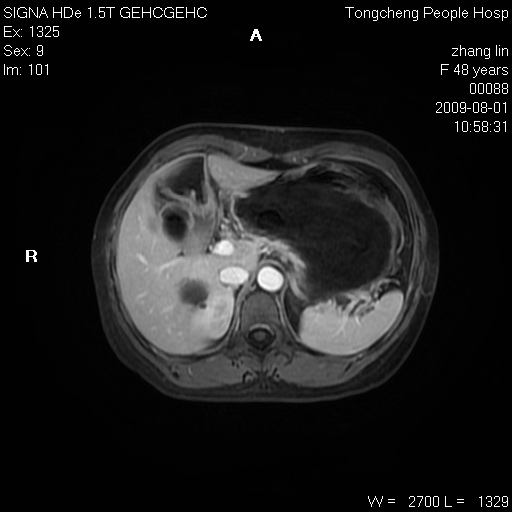

女,48岁。健康体检,彩超发现右肾占位性病变。平素健康。

临床诊断:右肾占位性病变,性质待定(囊肿?肿瘤?)。

上中腹部mr平扫+增强扫描,图像如下:

右肾上极见一类圆形病灶,t1wi呈等信号t2wi呈等高混杂信号,三期增强无强化,边界清---考虑囊肿出血。

同反相位均表现为等信号,病变无强化,考虑含蛋白的囊肿可能,弥散加权相或许有些帮助,

慢性胆囊炎